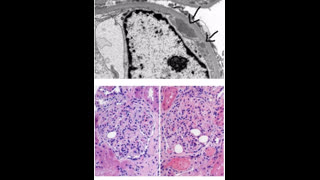

Answer is ( b) . AKI is due to haem induced acute kidney injury caused by cephalexin which has been associated with hemolytic anemia, AIN and ATN. Intravascular hemolysis results in release of hemoglobin/heme into the circulation, and is filtered in the nephrons,. haem moiety is nephrotoxic and causes cell injury and death in the renal tubular cells. Dark urine can be a sign of urinary pigment due to rhabdomyolysis, hyperbilirubinuria, or hemolytic anemia. low haptoglobin, high direct BR levels, high LDH level are suggestive of autoimmune hemolytic anemia due to drug exposure ( cephalexin). urine sediment shows RTECs, pigmented granular casts, and RTEC casts suggesting ATN mediated by iron deposits within RTECs. Urine sediment image shows Urinary cast with iron deposits which is well stained on May–Grünwald–Giemsa stain. Numerous iron deposits (hemosiderin granules) seen within the casts